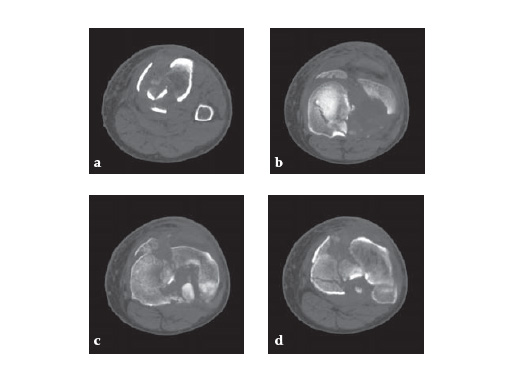

The LCP Medial Proximal Tibia Plates 3.5 and 4.5 are part of the LCP periarticular plating system. They are intended to buttress metaphyseal fractures of the medial tibia plateau, split-type fractures of the medial tibia plateau, medial split fractures with associated depressions and split or depression fractures of the medial tibia plateau. The plates may also be used for fixation of the proximal quarter (lateral and medial) of the tibia as well as segmental fractures of the proximal tibia. The 4.5 version may also be used for fixation of nonunions and malunions of the medial proximal tibia and tibia shaft, as well as opening and closing wedge tibial osteotomies.

57-year-old malemotor accident

Case provided by Phil Kregor, Nashville, USA